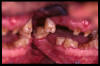

CM Unico diente remanente: el canino